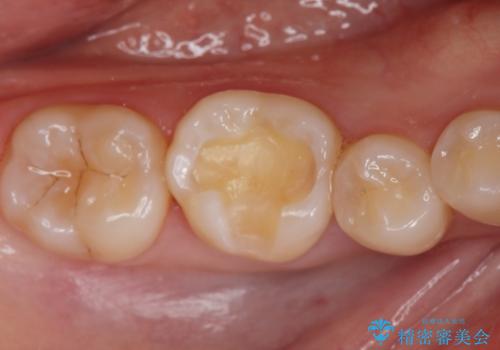

- 口を開けたとき銀歯が見えるのが嫌で白くしたいとの事で来院。

銀歯を除去してセラミックインレー(e-maxインレー)での治療となりました。

白い詰め物(e-maxインレー)にしたことにより、口を開けたとき目立たなくなりました。